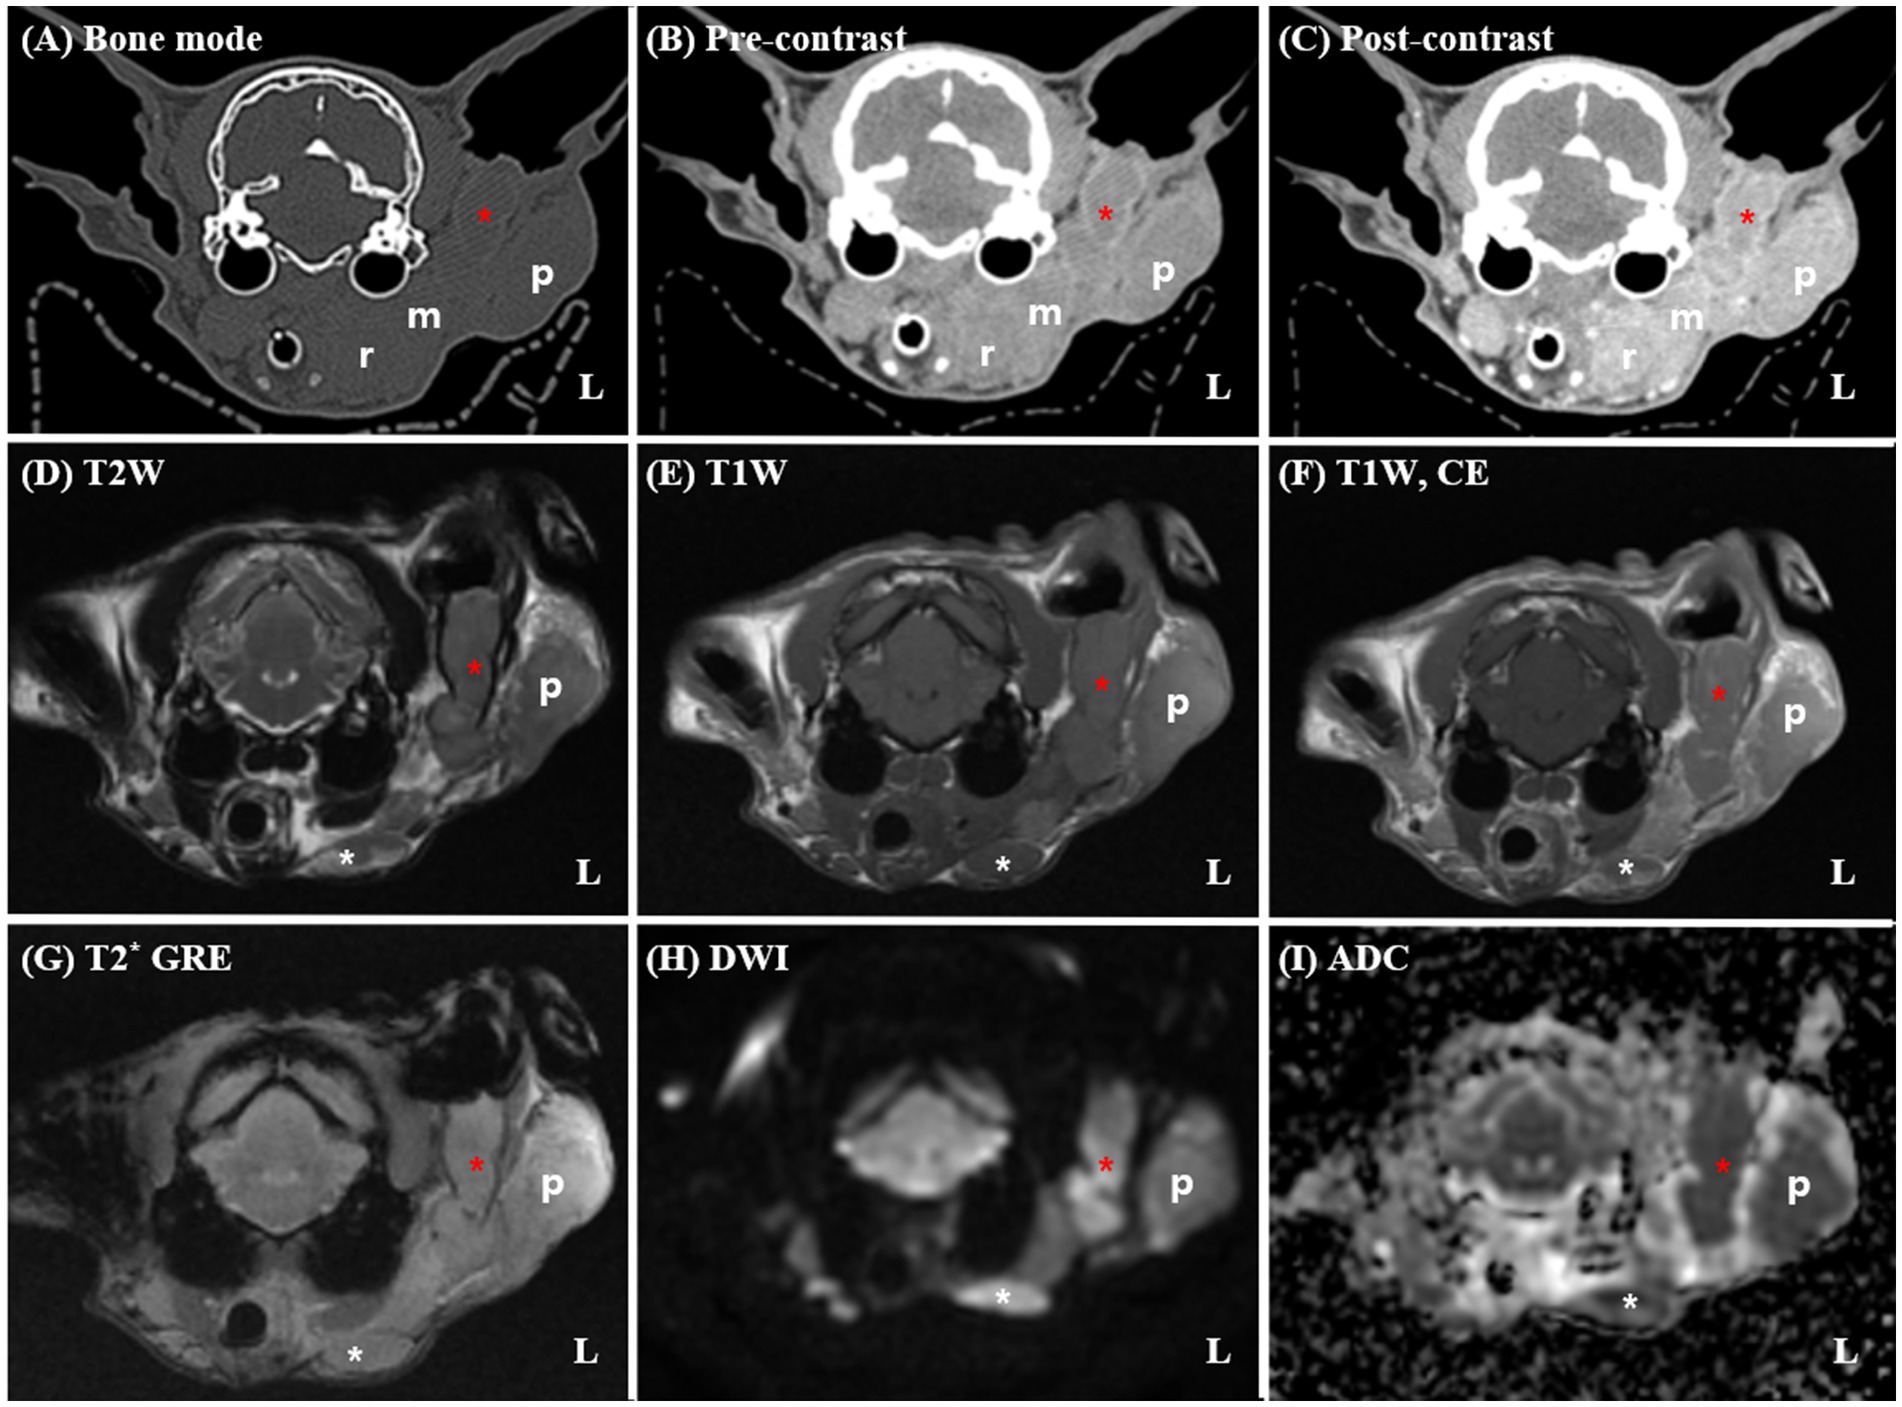

A 14-year-old spayed female Persian cat weighing 3.09 kg was referred to Seoul National University for evaluation of a mass in the left external ear canal. The cat had previously been diagnosed with ceruminous gland adenocarcinoma based on an incisional biopsy performed at a local veterinary clinic and was undergoing medical treatment with toceranib phosphate (2.5 mg/kg PO). Despite treatment, the cat developed worsening pruritus in the left external ear canal and progressive enlargement of the mass. The general condition remained stable, with a normal appetite, urination, and defecation reported by the owner. The cat was bright, alert, and responsive during the examination and showed no signs of systemic illness. Upon physical examination, the cat exhibited a body condition score of 3/9, with mild dehydration noted based on skin turgor. Moderate brown, waxy discharge and a firm, irregular mass were detected within the left external ear canal, accompanied by mild swelling of the surrounding parotid region. The palpebral reflex was absent in the left eye, suggestive of facial nerve dysfunction, while other cranial nerve reflexes were intact. No enlargement of the submandibular or prescapular lymph nodes was palpated, and no vestibular or gait abnormalities were observed. Pain response during manipulation of the ear region was mild, and the cat tolerated the examination well. Thoracic radiographs revealed no evidence of pulmonary metastasis, and hematological and biochemical profiles were within normal limits. To assess tumor extent and plan radiation therapy, contrast-enhanced CT and MRI scans were performed under general anesthesia using an 80-row, 160-multislice CT scanner (Aquilion Lightning®; Canon Medical Systems Co., Otawara, Japan) and a 1.5-T MRI scanner (SIGNA Creator; GE Healthcare, Milwaukee, WI, USA) equipped with an 8-channel flex coil. Cross-sectional imaging revealed a large, extensive soft tissue mass occupying the left vertical ear canal, causing complete luminal obstruction and extending into the adjacent parotid and mandibular regions (Figure 1). The mass demonstrated strong, homogeneous enhancement on contrast-enhanced images. The left masticatory muscles and mandibular salivary gland exhibited similar enhancement patterns with indistinct margins, suggesting direct tumor invasion. DWI MRI showed marked restricted diffusion within the mass, characterized by hyperintensity on DWI and corresponding hypointensity on ADC maps, indicative of high cellularity. The mean ADC value of the mass was measured at 397 × 10−6 mm2/s. Multiple ipsilateral lymph nodes, including the mandibular, medial and lateral retropharyngeal, and prescapular lymph nodes, were markedly enlarged, homogeneously enhanced, and exhibited similar diffusion restriction, raising concerns for metastatic involvement. The right medial retropharyngeal lymph node was mildly enlarged. No evidence of pulmonary metastasis, osseous destruction, or abnormalities in the tympanic bullae, nasal cavities, or brain parenchyma was noted. Based on CT and MRI findings, the tumor demonstrated extensive local invasion into adjacent soft tissues, including the parotid region, mandibular salivary gland, and masticatory muscles, rendering surgical excision unfeasible.

Figure 1. Pre-radiotherapy computed tomography (CT) (A–C) and magnetic resonance imaging (MRI) (D–I) findings in a 14-year-old spayed female Persian cat diagnosed with left ceruminous gland adenocarcinoma. The CT and MRI reveal a large soft tissue mass (red asterisks) occupying the left vertical external ear canal, with extension into the adjacent parotid (p) and mandibular regions. On post-contrast CT and T1-weighted MRI images (C,F), the mass demonstrates strong, homogeneous enhancement. The margins between the mass and surrounding structures, including the masseter muscle and mandibular salivary gland (m), are indistinct, suggesting direct invasion. Marked enlargement of the ipsilateral mandibular (white asterisks) and medial retropharyngeal (r) lymph nodes are noted. The left lateral retropharyngeal lymph node is not clearly distinguishable from the primary mass, raising suspicion of direct tumor infiltration. Additionally, the left prescapular lymph node and parotid gland are severely enlarged (not shown). No evidence of osseous destruction or middle ear involvement is observed. On DWI (G), the mass exhibits marked hyperintensity with corresponding hypointensity on the ADC map (H), consistent with restricted diffusion and high cellularity. T1W, T1-weighted imaging; T2W, T2-weighted imaging; DWI, diffusion-weighted imaging; T1CE, post-contrast T1-weighted imaging; T2*, T2-weighted imaging; ADC, apparent diffusion coefficient.